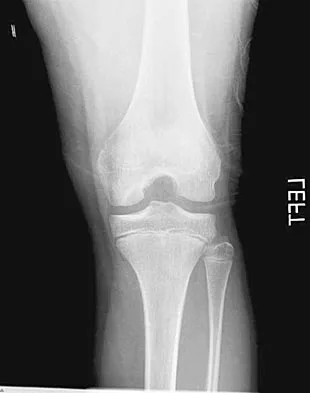

A 28-year-old man has had a 2-year history of progressive lateral ankle pain. History reveals that he underwent a triple arthrodesis at age 13 for a tarsal coalition. The pain has been refractory to braces, custom inserts, and nonsteroidal anti-inflammatory drugs. Weight-bearing radiographs of the ankle and foot are shown in Figures 3a through 3d. Surgical management should include which of the following?